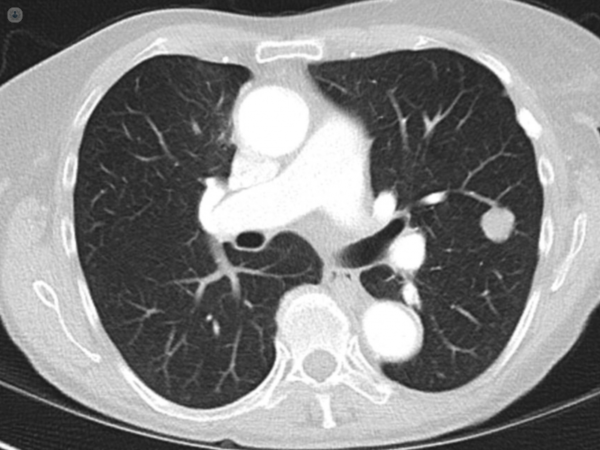

Un nódulo pulmonar solitario, a menudo denominado “lesión de moneda” debido a su forma redondeada y aislada, es una opacidad circunscrita en la imagen de tórax, generalmente de menos de 3 centímetros de diámetro, delimitada por un pulmón aparentemente normal. Su identificación en imágenes radiográficas o en tomografías computarizadas es un hallazgo importante que requiere una evaluación cuidadosa debido a la diversidad de su posible etiología.

Estos nódulos pueden ser clasificados en sólidos, subsólidos con vidrio esmerilado o de consistencia mixta. La mayoría de ellos son asintomáticos y se descubren incidentalmente durante estudios de imagen realizados por otras razones. Su aspecto redondeado y aislado en el contexto de un pulmón normal sugiere que están bien delimitados y no asociados con otras anomalías pulmonares.

La evaluación de un nódulo pulmonar solitario para determinar su probabilidad de malignidad se basa en una combinación de datos clínicos y características radiográficas. La tomografía computarizada (TC) juega un papel crucial en esta evaluación debido a su capacidad para proporcionar una visión detallada del nódulo y de su entorno.